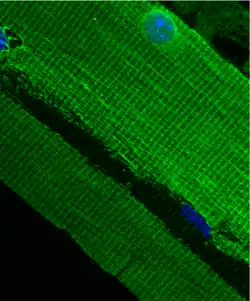

Costamere structure in mouse quadriceps | |

The costamere is a structural-functional component of striated muscle cells[1] which connects the sarcomere of the muscle to the cell membrane (i.e. the sarcolemma).[2]

Costameres are sub-sarcolemmal protein assemblies circumferentially aligned in register with the Z-disk of peripheral myofibrils.[3][4][5] They physically couple force-generating sarcomeres with the sarcolemma in striated muscle cells and are thus considered one of several "Achilles' heels" of skeletal muscle, a critical component of striated muscle morphology which, when compromised, is thought to directly contribute to the development of several distinct myopathies.[6]